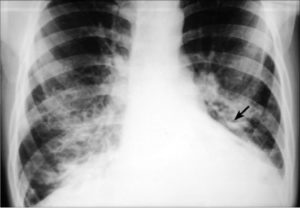

На прямой обзорной рентгенограмме прослеживается усиление, деформация легочного рисунка за счет интерстициальных изменений, распространенного пневмосклероза. Простым языком такое заключение можно объяснить искривлением бронхов, вокруг которых деформирован ход сосудов. Вокруг патологических участков прослеживается разрастание соединительной ткани.

Рентгенограммы: усиление рисунка и затемнение в нескольких сегментах нижней доли справа

Цифровой снимок при интерстициальном пневмокониозе: сгущение и усиление рисунка в верхних и средних долях, эмфизематозность снизу с обеих сторон